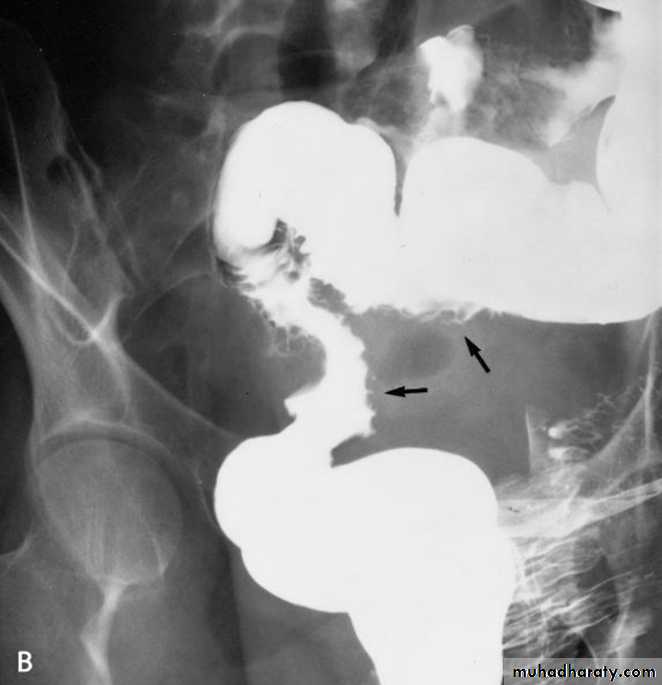

•Diverticular disease of the colon

• Due to over activity and hypertrophy of transverse bands of smooth muscle which result in increased intra-luminal tension with herniation of mucosa through week point in the wall.The condition is commonly seen in left hemi-colon.Radiological appearance:Plain film: show air trapping .• Ba. Enema :

• *Early appearance show saw-teeth colon (pre-diverticular stage).• *The diverticulum is consist of body and neck , best seen in post evacuation film .

• *Faecal impaction may result in incomplete filling of the body or flask shape .

• Complication of diverticular disease

• 1- Diverticulitis(inflammation & infection). 2- Ulceration and haemorrhage . 3- Perforation …. Pneumo-peritonium . 4- Fistula … air fluid level in bladder , or sinus track . 5- Peri-colic abscess….localized narrowing . 6- Intestinal Obstruction …. Air fluid level . 7- Malignant change …. Irregular narrowingcongenital anomaly of the colon: